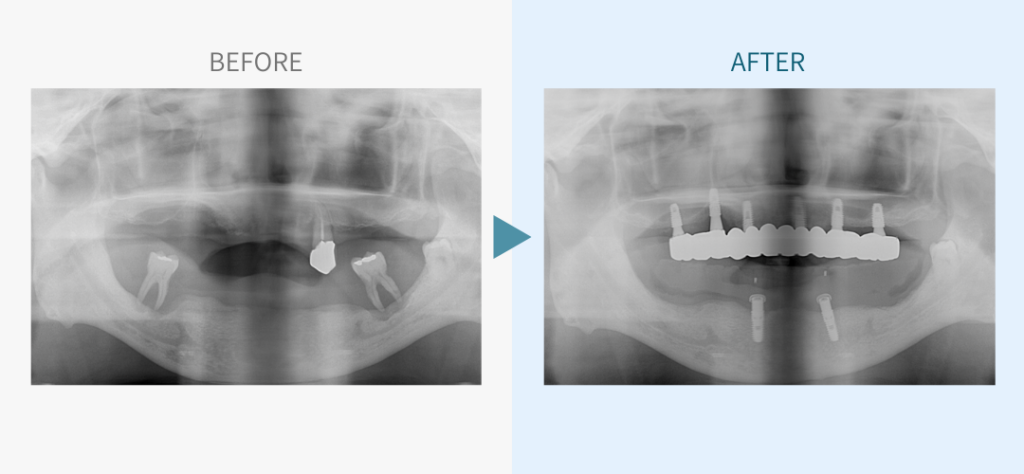

デンタルチームジャパンでは、サイナスリフト(上顎洞底挙上術)や骨造成など、他院で「骨が足りない」と断られた難症例にも対応しています。

私たちは、難症例に関する治療法を学会でも発表しており、その豊富な実績と技術力が評価され、全国から患者様が来院いただいております。

こちらではその一部の症例についてご紹介します。